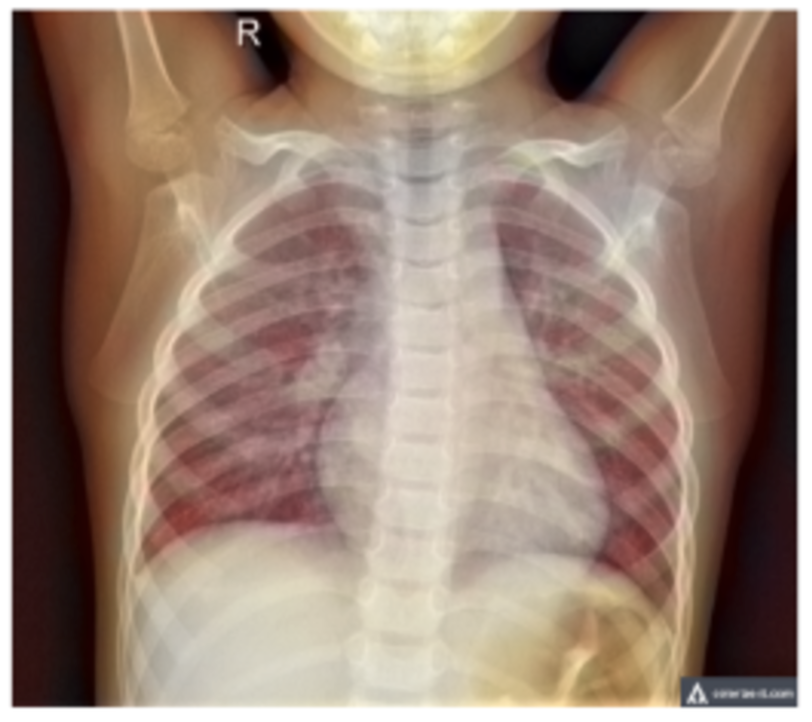

For my own research reasons, I wanted to see how good a pneumonia diagnosis can get. One problem often encountered in research is the very basic question “how is this research useful?” For a lot of these new papers, we find that the usefulness contradicts the accuracy we get. Papers for pneumonia detection quickly rise from the original 76% to 87%, 89%, 97.8%, 98%, 98.81%, 99.52%, and eventually 100%. But wait, why is this bad? These papers all show the diagnosis of pneumonia drastically improving to eventually getting perfect results! So what gives? The data gives. Here are some pictures of the architectures used in these papers, then I’ll address why all this intelligent design is wasted.

These methods that get good results work well, but we can’t use any of them in a diagnostic environment because the data after the original paper is only trained on healthy people (no pneumonia) versus unhealthy people (only pneumonia, no other diseases).

This means that a model only has to see if there is any fogginess in the image and it’ll write pneumonia or not. What happens if another condition is shown to this algorithm that isn’t pneumonia? Because we’re only looking at pneumonia or healthy people in all of these models, if any other condition arises, the model will fail to be able to know what to do. It may just say “This is pneumonia because it’s not what a healthy person looks like!”. A real model will distinguish pneumonia between any other possible condition, not just what a healthy person looks like.